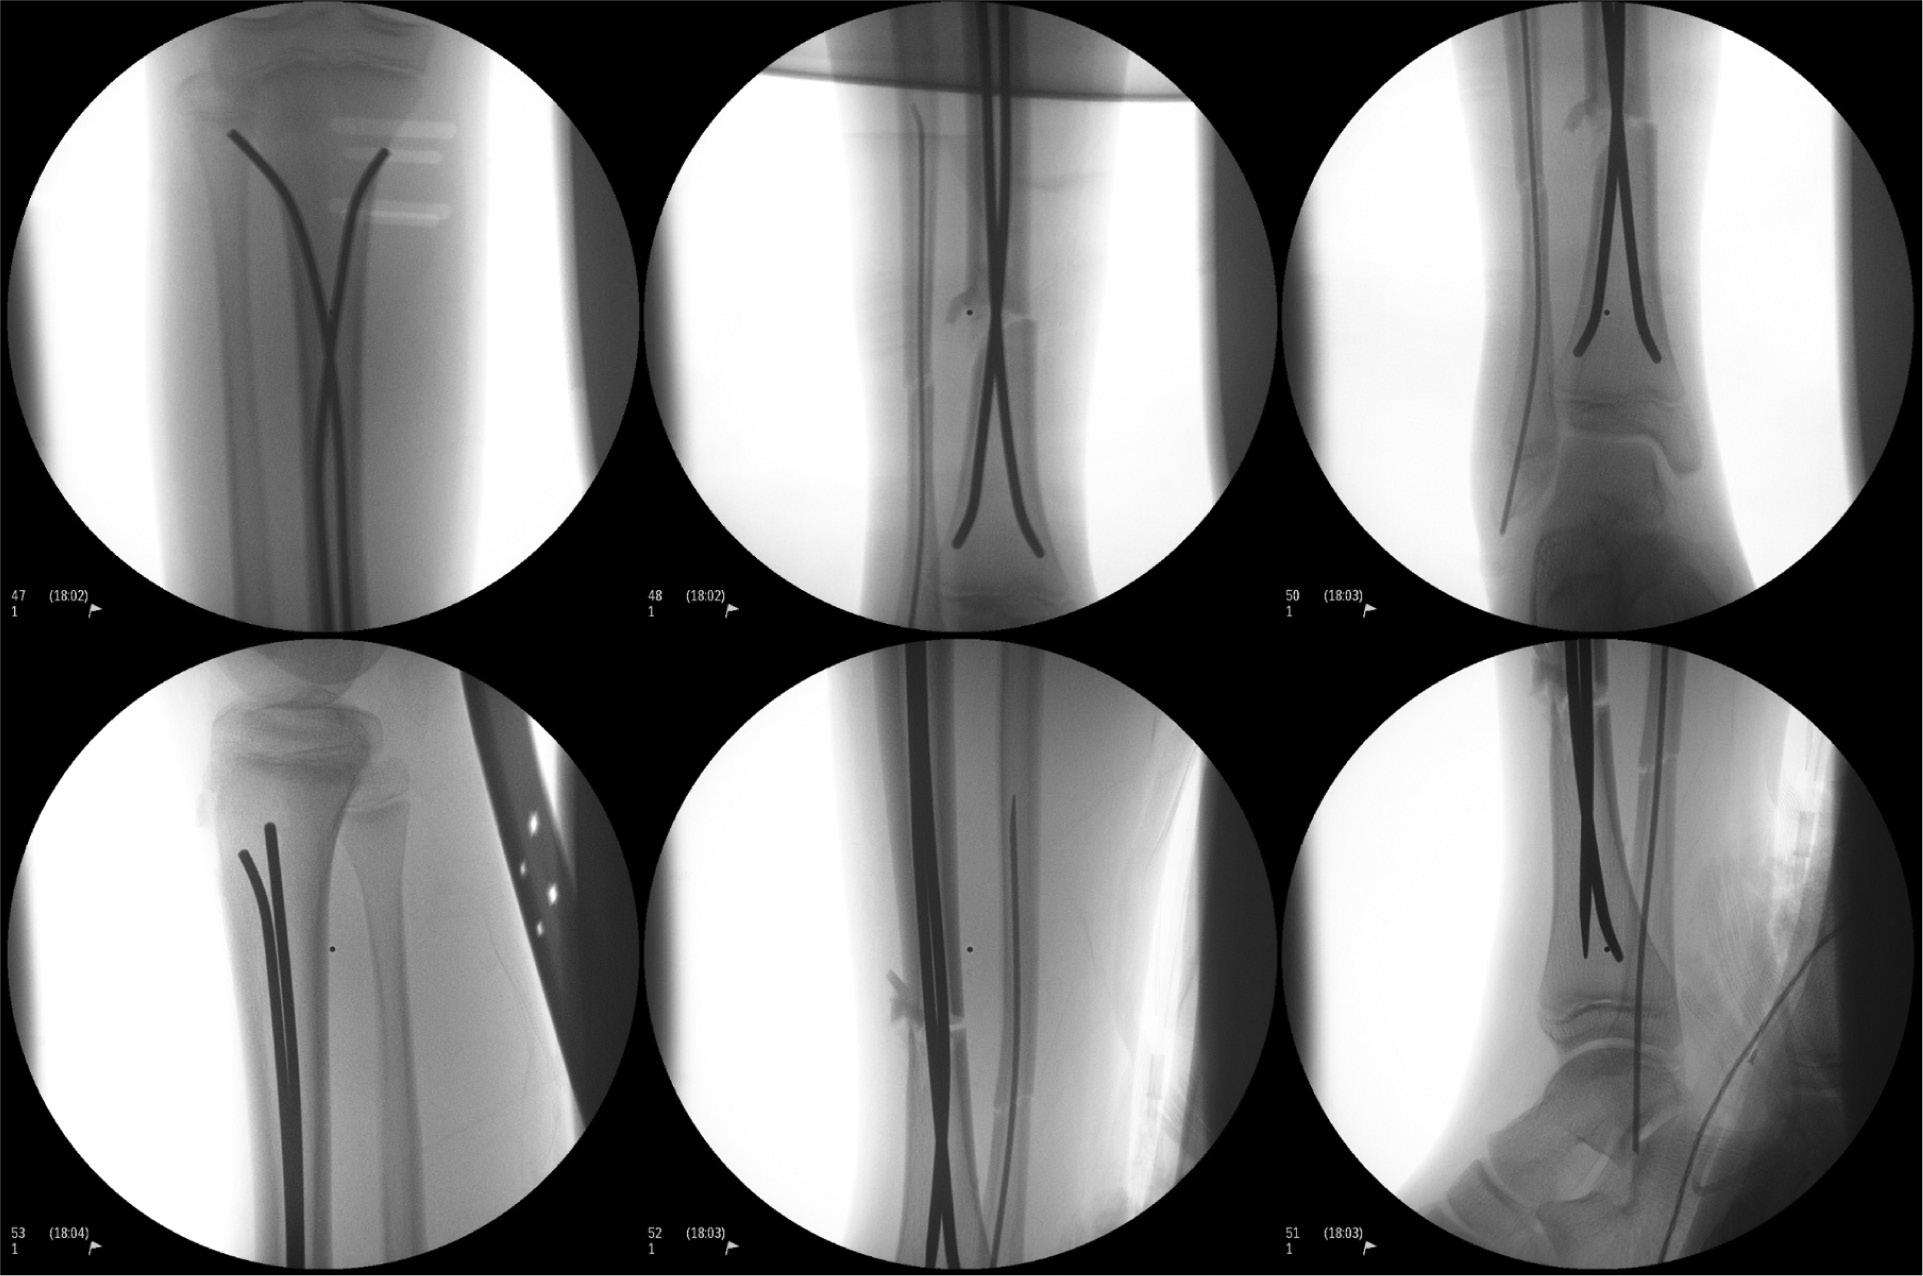

Final fluoroscopy:

- Difficulty with closed reduction, due to some of the comminution. Able to achieve good reduction by applying axial traction using radiolucent triangles and stack of blue OR towels.

- Tibia: 3.5 mm stainless steel ESINs

- Notice distally how the nails cross essentially right at the fracture. This is not ideal, but sometimes there is no way around this.

- Fibula: 1.5 mm titanium ESIN

- Decided to augment our tibial fixation with fixation of the fibula due to there being lateral comminution at the fracture on the tibia. We thought that by adding some stiffness/fixation to the fibula, we could help prevent the tibia from translating laterally and/or falling into valgus.